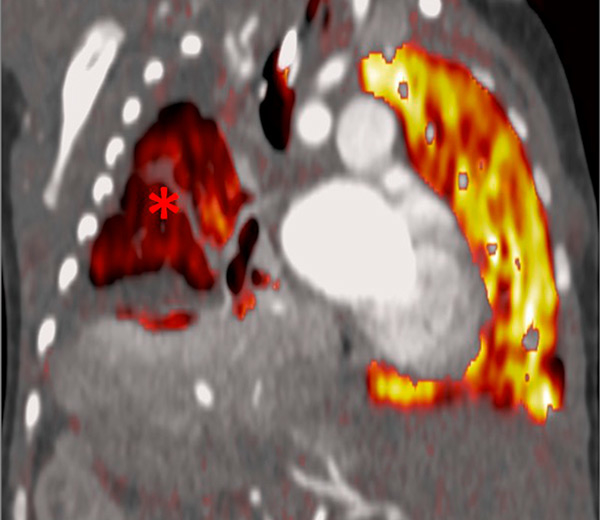

Figure 6

Perfusion heterogeneities in idiopathic pulmonary artery hypertension (stars) in two different patients (A/B). The dilatation of the arteries in pulmonary hypertension (arrows) is not always observed depending on the severity of pulmonary hypertension.